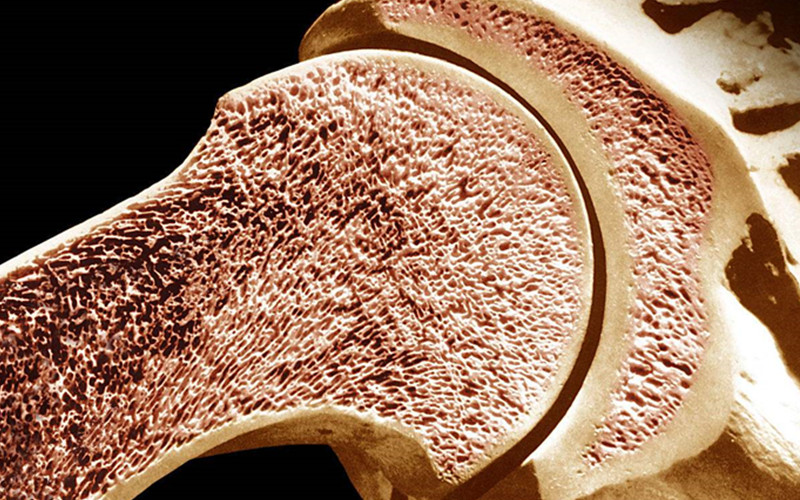

远离“脆骨”添密度

可别以为骨质疏松只是老年人的专利,现代人吃饭不规律,饮食习惯差,骨质疏松,可是越来越有低龄化的趋势。补了那么多钙进去,得加强骨密度,留住钙质,才是巩固骨骼健康的根本。

维生素K2是钙代谢的关键控制因子,补充维生素K2,就像给骨骼增加了密度,腾出了更多吸收钙元素的空间。澳洲Bio Island牛乳钙中的钙元素,提取自天然的澳洲牛乳,维生素D加维生素K2的黄金组合,能帮助骨骼吸收巩固更多的钙质。

饮食补充维生素K2,好似杯水车薪。对于钙吸收较差、骨骼密度十分疏松的人,单独补充维生素K2才是好方法。维生素K2进入人体后,能帮助钙质沉积到骨骼,避免在钙元素在消化过程中被其他器官所吸收。所以,对于身体机能衰退的中老年人来说,补钙的同时补充一些维生素K2,才能更好地增强骨密度,改善骨质疏松的困扰。